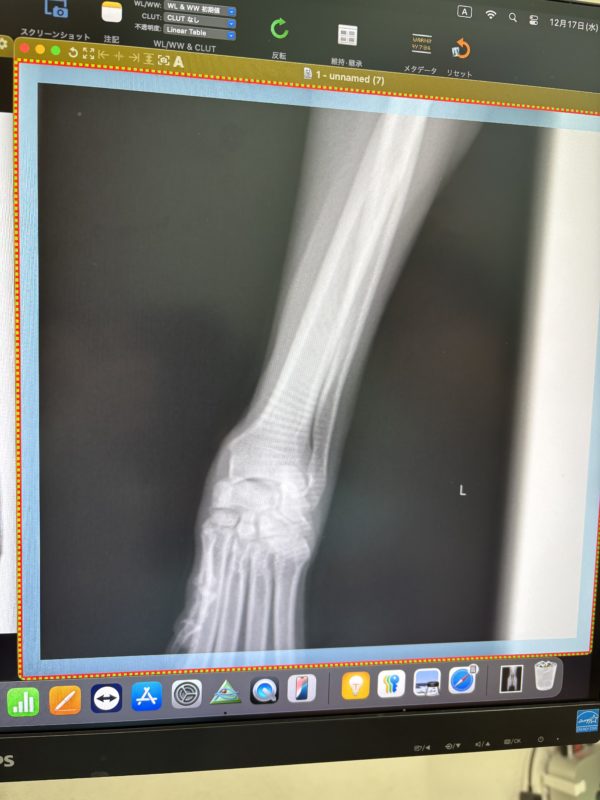

私には何がどうだか全く分からない画像ですが

骨折もヒビすら見受けられないとのことでホッ😌

靭帯やひどい捻挫ならレントゲンにも映ることがあるそうですが

それも見受けられないとのことで